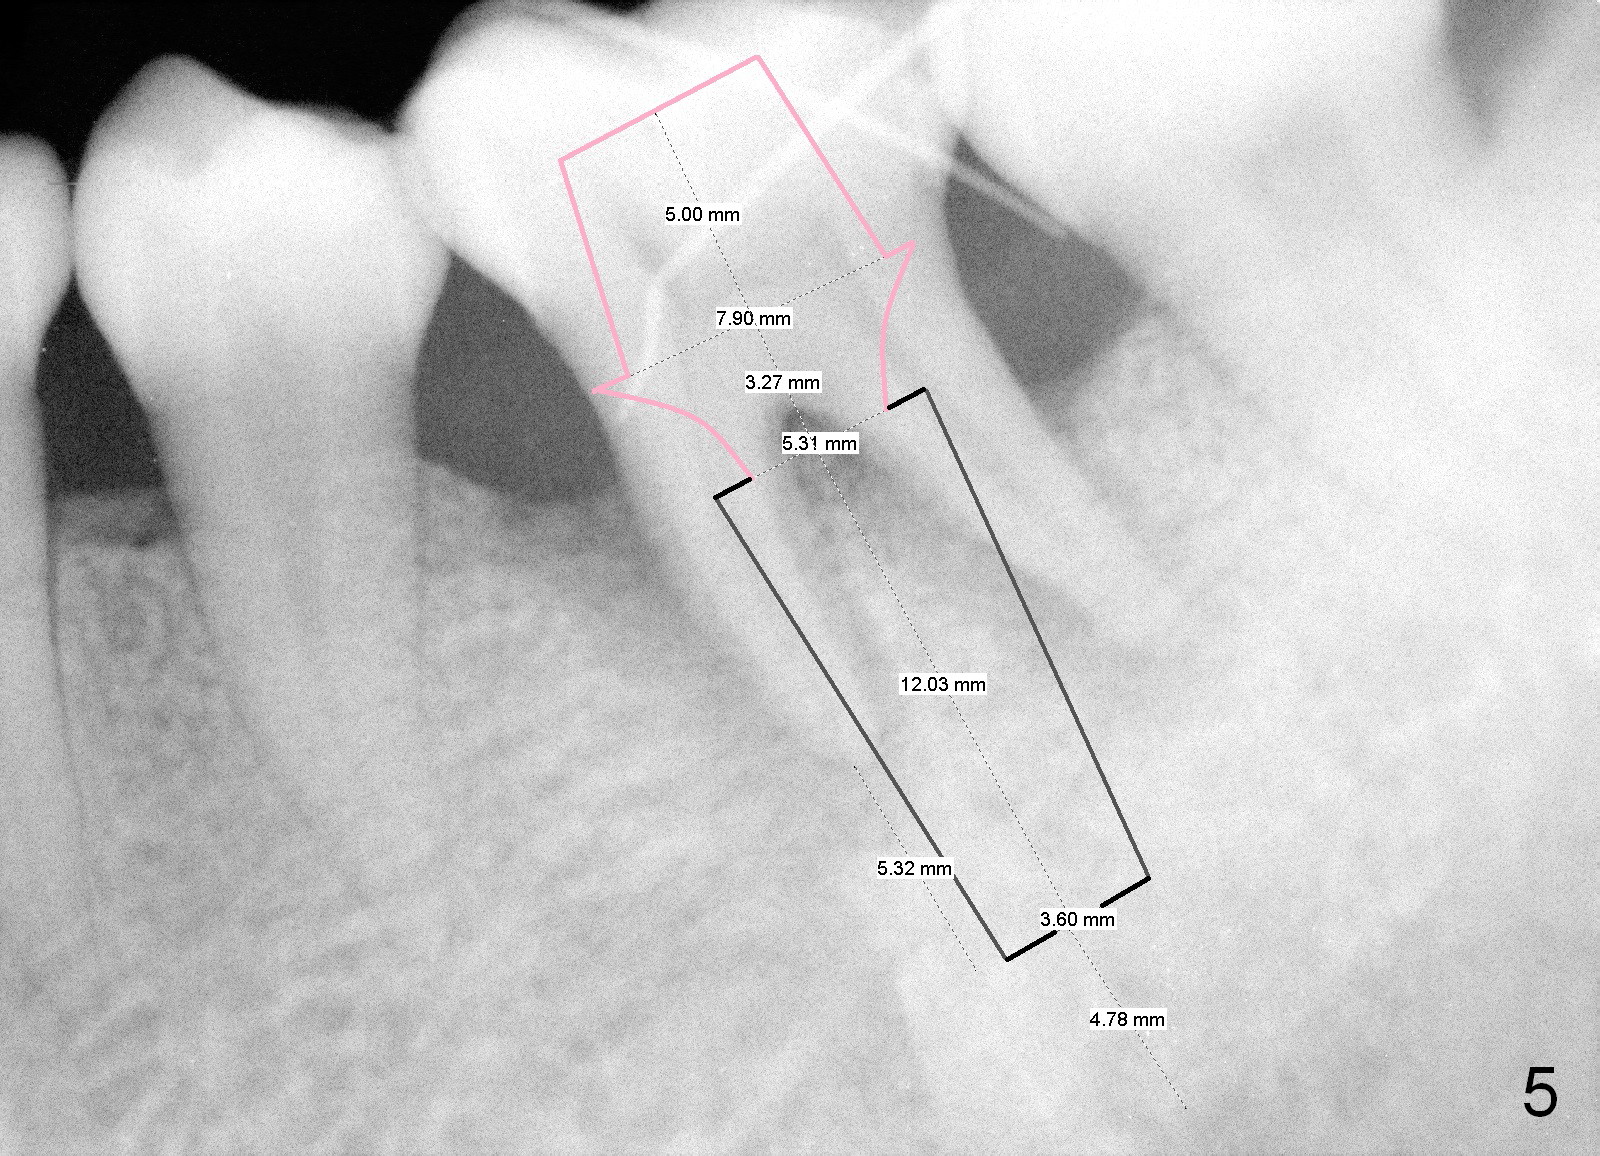

A 43-year-old lady has generalized moderate localized advanced chronic periodontits (Fig.1,2). In spite of 4 quadrant scaling & root planing, the tooth #19 develops 2 perio abscesses (Fig.4 with insertion of 2 guttae perchae); periodontal ligament spaces increases (compare Fig.2,4). It appears that the tooth is non salvageable and should be replaced with an immediate implant (Fig.5). The extraction socket will be treated with Metronidazole. A 2 mm pilot drill is used to start osteotomy in the septum (14 mm deep), followed by reamers until 3.5 mm. A 5x17 mm tap is placed to test stability. If the stability is high, place a 5.3x12 mm SM implant. If insertion torque is too high, use the corresponding drill before re-place the implant. Collagen dressing is placed in the peripheral and deep portion of the sockets, while bone graft in the top portion of the sockets (near implant threads). Use 1 or 2 amalgam carriers to deliver the graft lateral to the implant precisely so that a cover screw does not have to be placed. Next place a cemented abutment. If trajectory of the implant is correct, an abutment as large as 7.8x5(3) mm could be used (pink). Fabricate an immediate provisional. Do not over trim the margin of the provisional so that it can cover the socket completely.